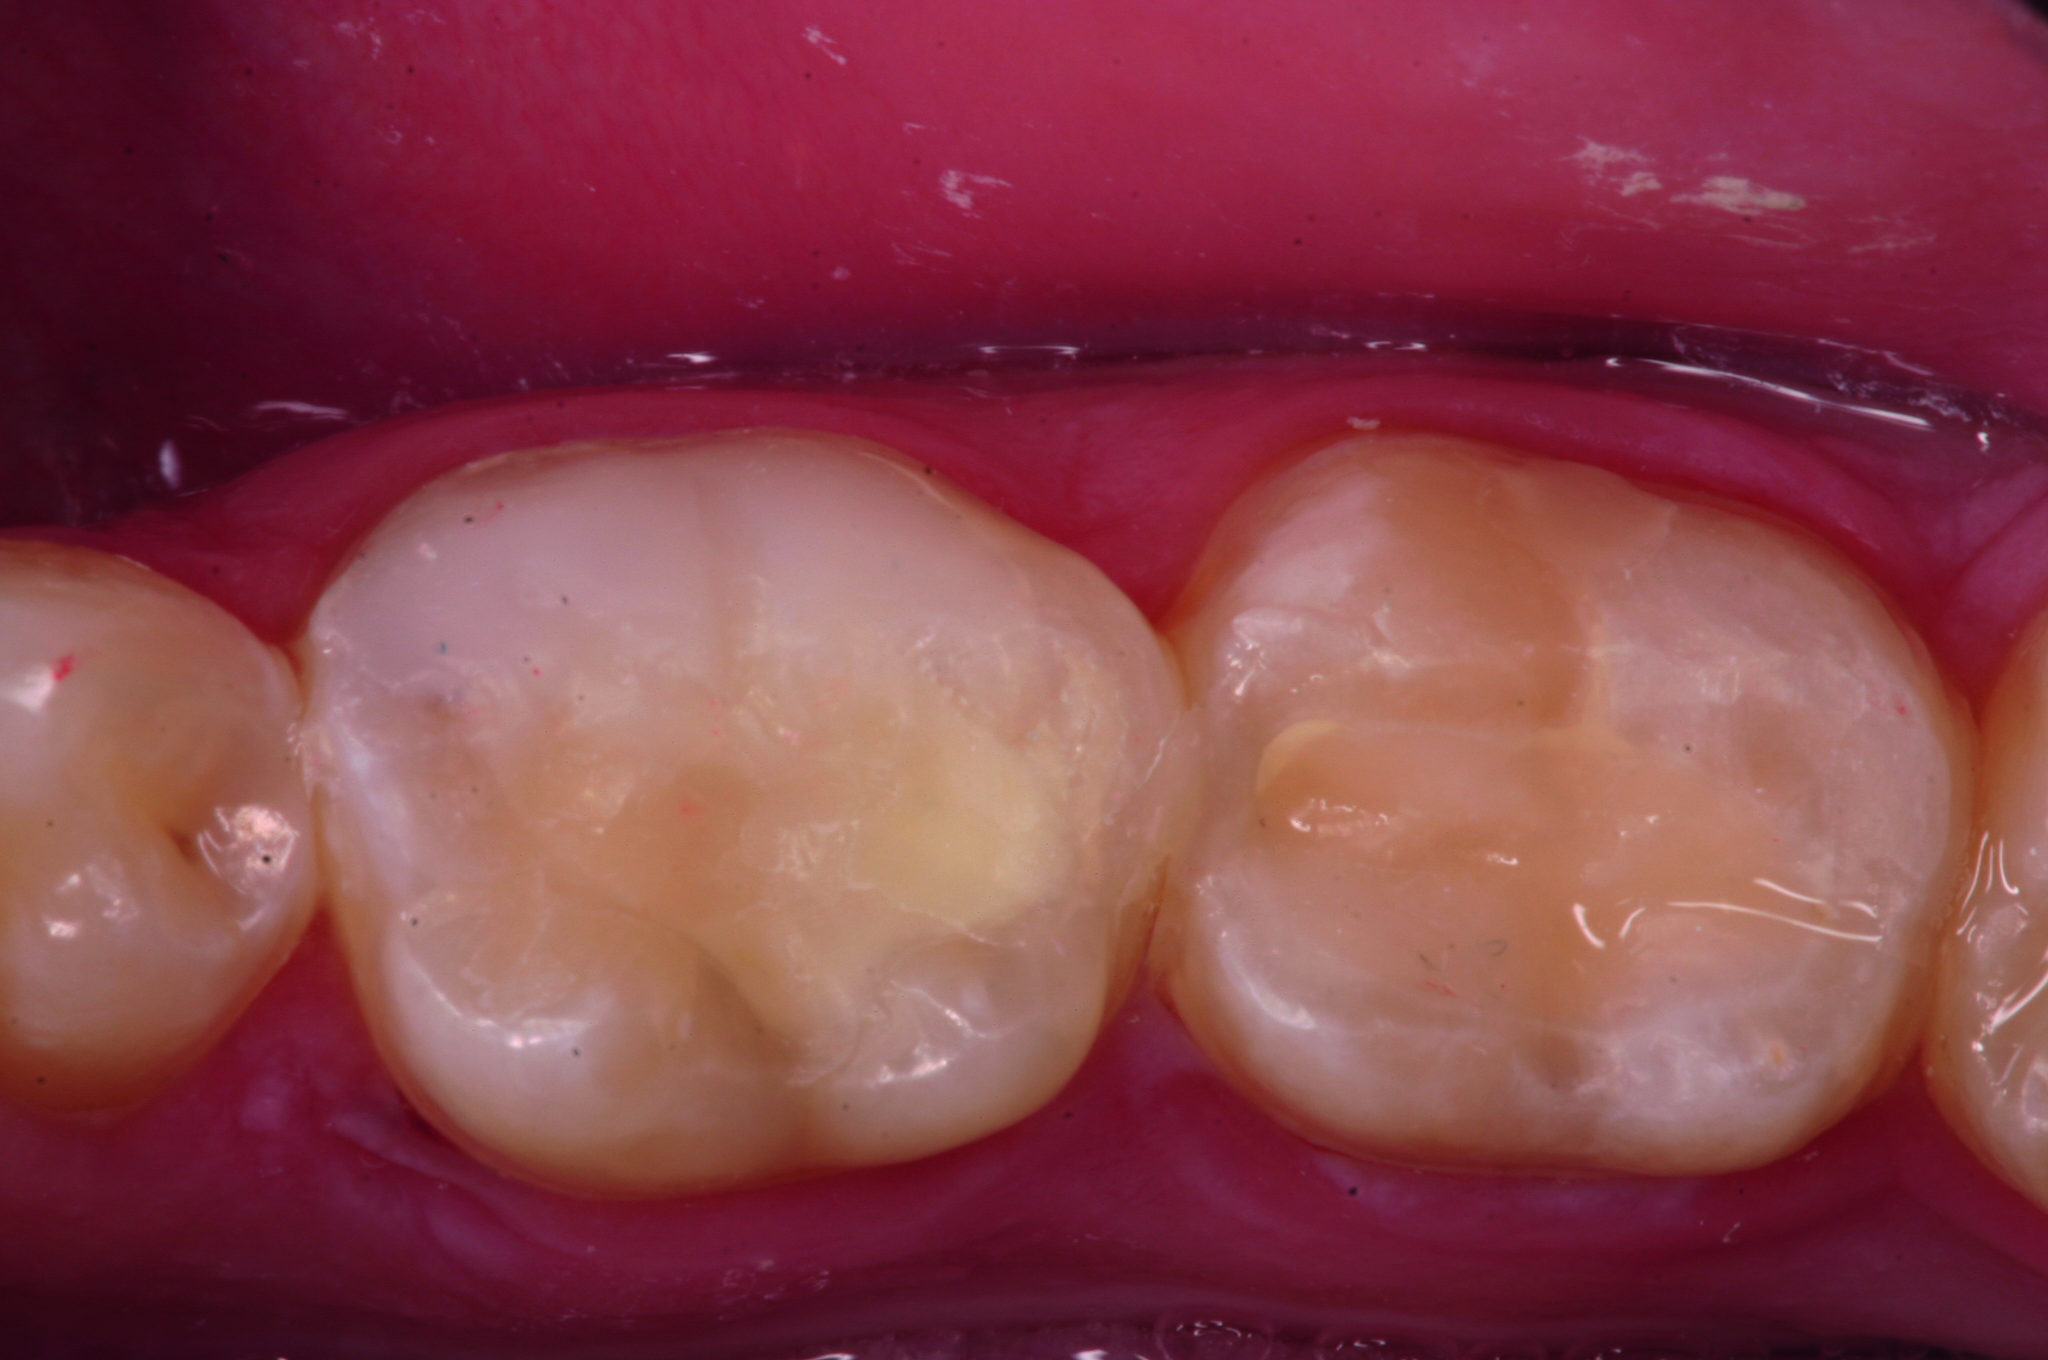

Fig. 1 : Situation préopératoire. (Photos : Joseph Sabbagh)

L’examen clinique a révélé plusieurs restaurations défectueuses et des caries occlusales sur les premières et deuxièmes molaires inférieures gauches (N° 36 et n° 37 [Fig. 1]).